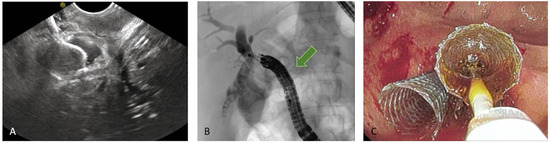

Figure 8. EUS-guided hepaticogastrostomy (HGS). (A) Puncture of the intrahepatic duct, EUS view; (B) puncture of the intrahepatic duct, radiologic image; (C) placement of a plastic stent to ensure biliary drainage.

HGS has become a crucial therapeutic option in cases where conventional ERCP fails or is contraindicated, particularly in patients with SAA, malignant duodenal obstruction, or inaccessible ampulla. HGS creates a permanent fistula between the intrahepatic ducts (typically segment II or III) and the gastric lumen, using a hybrid SEMS specifically designed for EUS-guided HGS. It is a partially covered hybrid stent with two functional segments: the intrahepatic portion is uncovered, allowing anchorage within the liver parenchyma, while the gastric portion is fully covered and equipped with an anti-migration flange, minimizing the risk of bile leakage and stent dislodgement [38]. Before the advent of dedicated hybrid stents, and in centers where these devices are not available, plastic stents have been used (Figure 8); in this setting, a long stent is suggested to avoid dislodgement [46]. Technical aspects include careful puncture to avoid vascular structures, gentle dilation of the tract, and deployment of covered SEMS to minimize bile leak.

Systematic reviews and multicenter series report technical success above 90% and clinical success around 80–90%. AEs, occurring in 10–20%, include the risks of persistent fistula and bile leak (which may be life-threatening if not promptly recognized), bleeding and peritonitis. Compared with PTBD, HGS is associated with fewer reinterventions and greater patient comfort; compared with antegrade stenting, it is easier to repeat but involves creating a transmural fistula with its own risks. Recent meta-analyses revealed technical success around 94.4% and clinical success around 88.6%, albeit with a higher overall adverse event rate (about 23.8%). HGS can also be performed as rescue option, once an EUS-HRV or an antegrade drainage fails [47].